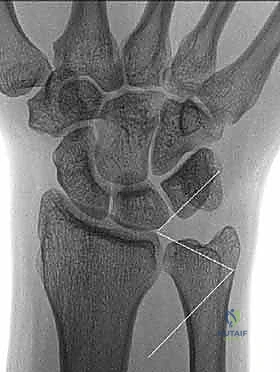

أي كسر يطال هذا العظم الحيوي، سواء كان في الناتئ الإبري (النتوء العظمي الصغير في نهاية الزند)، أو رأس الزند (الجزء المفصلي)، أو الجزء الكردوسي الكردوسي (المنطقة الانتقالية بين الرأس وجسم العظم)، يمكن أن يؤدي إلى خلل ميكانيكي عنيف. هذا الخلل غالبًا ما يترجم إلى عدم استقرار في المفصل الزندي الكعبري البعيد (Distal Radioulnar Joint - DRUJ)، مما يسبب آلامًا مزمنة، وضعفًا في قبضة اليد، وتآكلًا غضروفيًا مبكرًا إذا لم يتم تشخيصه وعلاجه بدقة متناهية.

- المفصل الزندي الكعبري البعيد (DRUJ): هو المفصل الذي يربط بين نهايات الكعبرة والزند عند المعصم. يدور عظم الكعبرة حول رأس الزند من خلال هذا المفصل أثناء حركات الكب (تدوير الساعد بحيث يكون باطن اليد لأسفل) والبسط (تدوير الساعد بحيث يكون باطن اليد لأعلى). استقرار هذا المفصل لا يعتمد فقط على العظام، بل يعتمد بشكل كبير على التوافق العظمي بين رأس الزند والثلمة الكعبرية (الشق السيني - Sigmoid Notch) في الكعبرة.

* كسور قاعدة الناتئ الإبري (Base Fractures): هي الأخطر. نظرًا لأن الأربطة الرئيسية للـ TFCC تتصل بقاعدة الناتئ، فإن الكسر هنا يعني غالبًا فقدان استقرار المعصم. يتطلب هذا النوع تقييمًا دقيقًا جدًا لمدى ثبات المفصل بعد تثبيت كسر الكعبرة (إن وجد).

3. كسور الجزء الكردوسي الكردوسي (Ulnar Metaphyseal Fractures)

الجزء الكردوسي هو العنق أو المنطقة الانتقالية التي تربط رأس الزند بجسم العظم (Diaphysis).

هذه المنطقة تحتوي على عظم إسفنجي (Cancellous bone) وهي عرضة للكسور المفتتة (Comminuted fractures) خاصة عند كبار السن المصابين بهشاشة العظام، أو في حالات الحوادث عالية الطاقة. الكسر هنا يؤدي إلى قصر في طول عظم الزند، مما يغير من ميكانيكية توزيع الأحمال في المعصم ويسبب متلازمة انحشار الزند (Ulnar Impaction Syndrome).